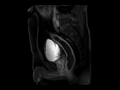

Rectal cancer

MRI images demonstrate a subtle rectal cancer at the 12 o clock position without evidence of extension into the mesorectal fat.